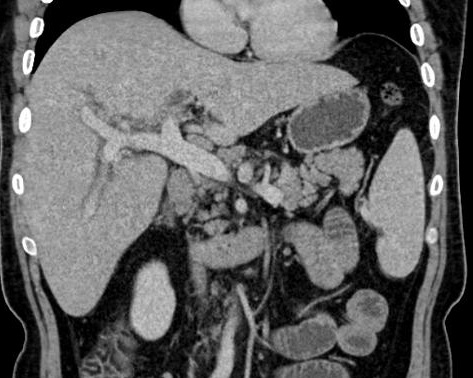

Image d'une pyleplebite de veine

mesenterique supperieure ( fleche jaune ) .

Sa paroi est epais et hyperdensite

etre en vue tres nette ( fleche jaune ) sur ce coupe . Image radiologique TDM en coupe

coronal ( frontal ) |